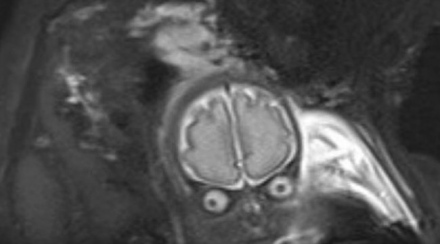

Az angliai Bury-ben élő fiatal pár, Laura Thomas és Matthew Tansley majdnem sokkot kaptak, amikor a nőgyógyásznál meglátták a 30 hetes magzatukat egy ultrahangfelvételen.